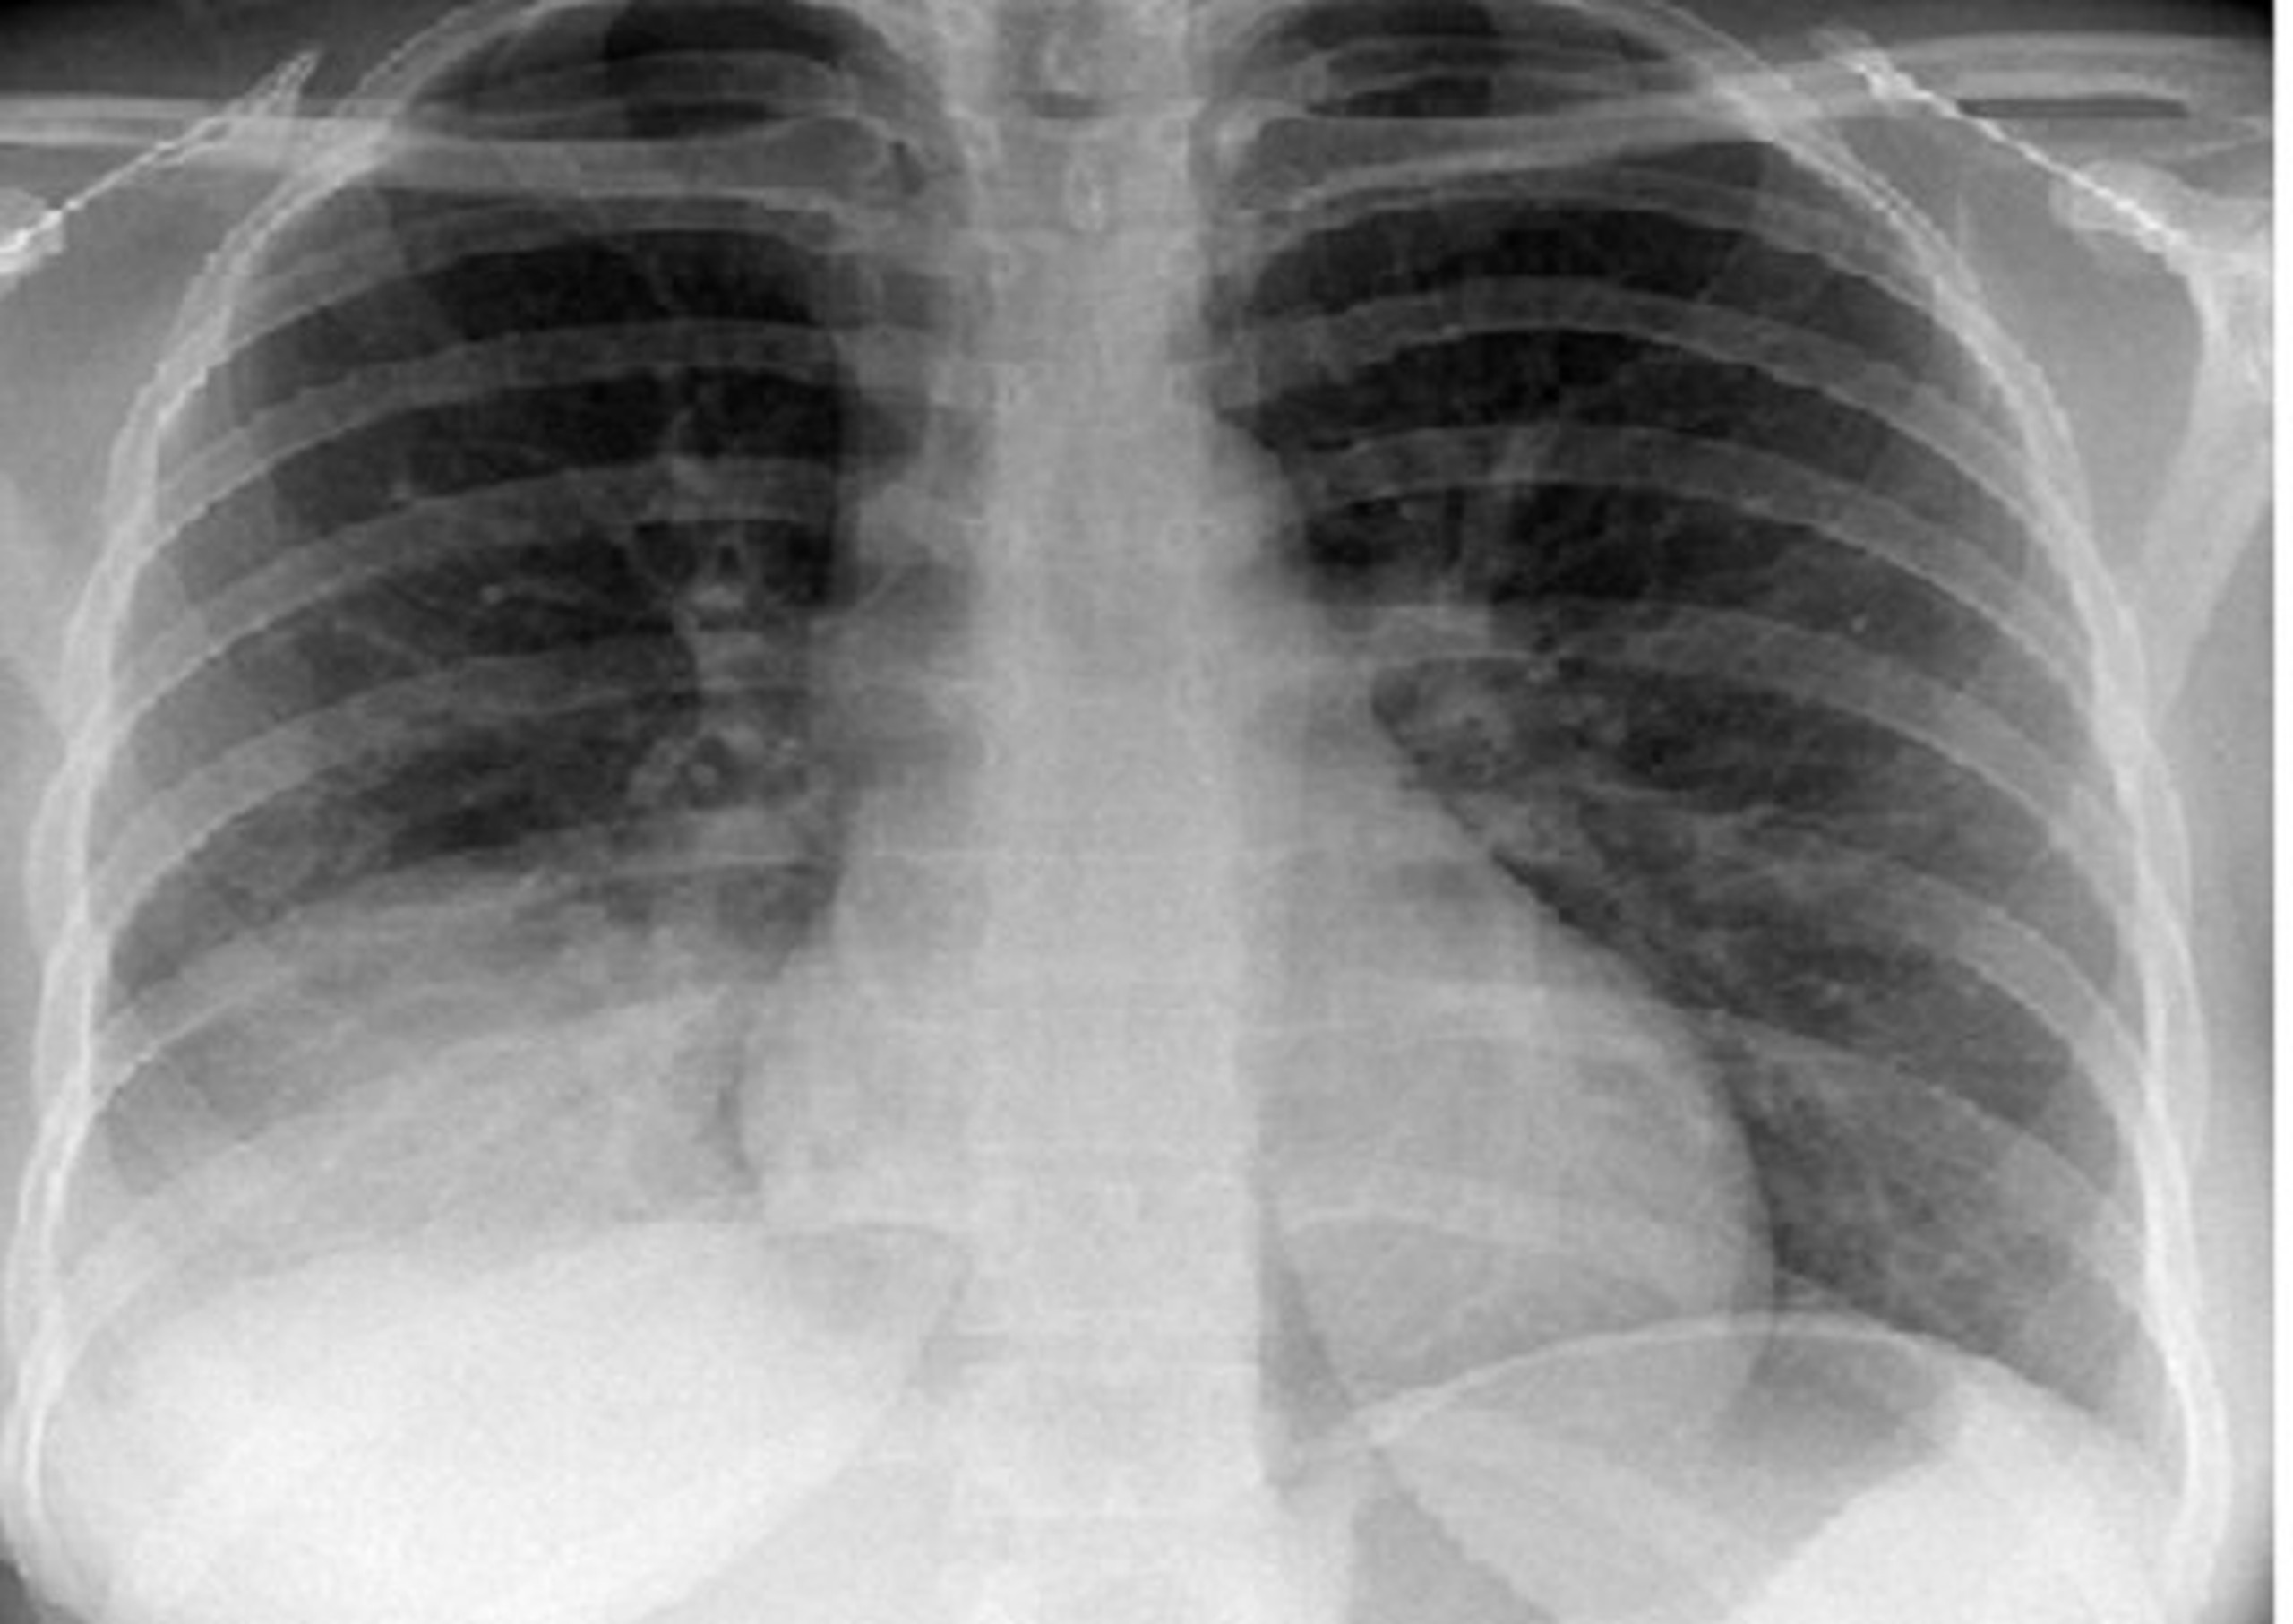

Khi một cơ quan nào trong cơ thể xảy ra vấn đề thì đều gây ảnh hưởng đến sức khỏe, đặc biệt khi cơ quan đó là phổi. Đóng vai trò quyết định trong việc trao đổi khí giữa cơ thể và môi trường bên ngoài, phổi thường xuyên tiếp xúc với các tác nhân lạ nên khả năng cao bị bệnh lý gây tác động đến hệ hô hấp. Một trong số những bệnh nguy hiểm và đáng chú ý là xẹp phổi với tỷ lệ ngày càng gia tăng. Xẹp phổi là căn bệnh liên quan đến đường hô hấp với các biến chứng nguy hiểm, thậm chí đe dọa tính mạng nếu không được điều trị kịp thời. Hãy cùng Long Châu tìm hiểu nguyên nhân, triệu chứng, chẩn đoán và điều trị xẹp phổi sẽ giúp bạn tự bảo vệ bản thân và có biện pháp phòng tránh thích hợp.

Xẹp phổi: Bệnh lý xảy ra ở đường hô hấp khi phổi hoặc các thùy phổi rơi vào trạng thái bị xẹp một phần hay toàn bộ dẫn đến các túi nhỏ phế nang không giãn nở như bình thường khi cơ thể thực hiện động tác hít - thở mà có chiều hướng bị xẹp (giảm thể tích) hoặc chứa đầy dịch.